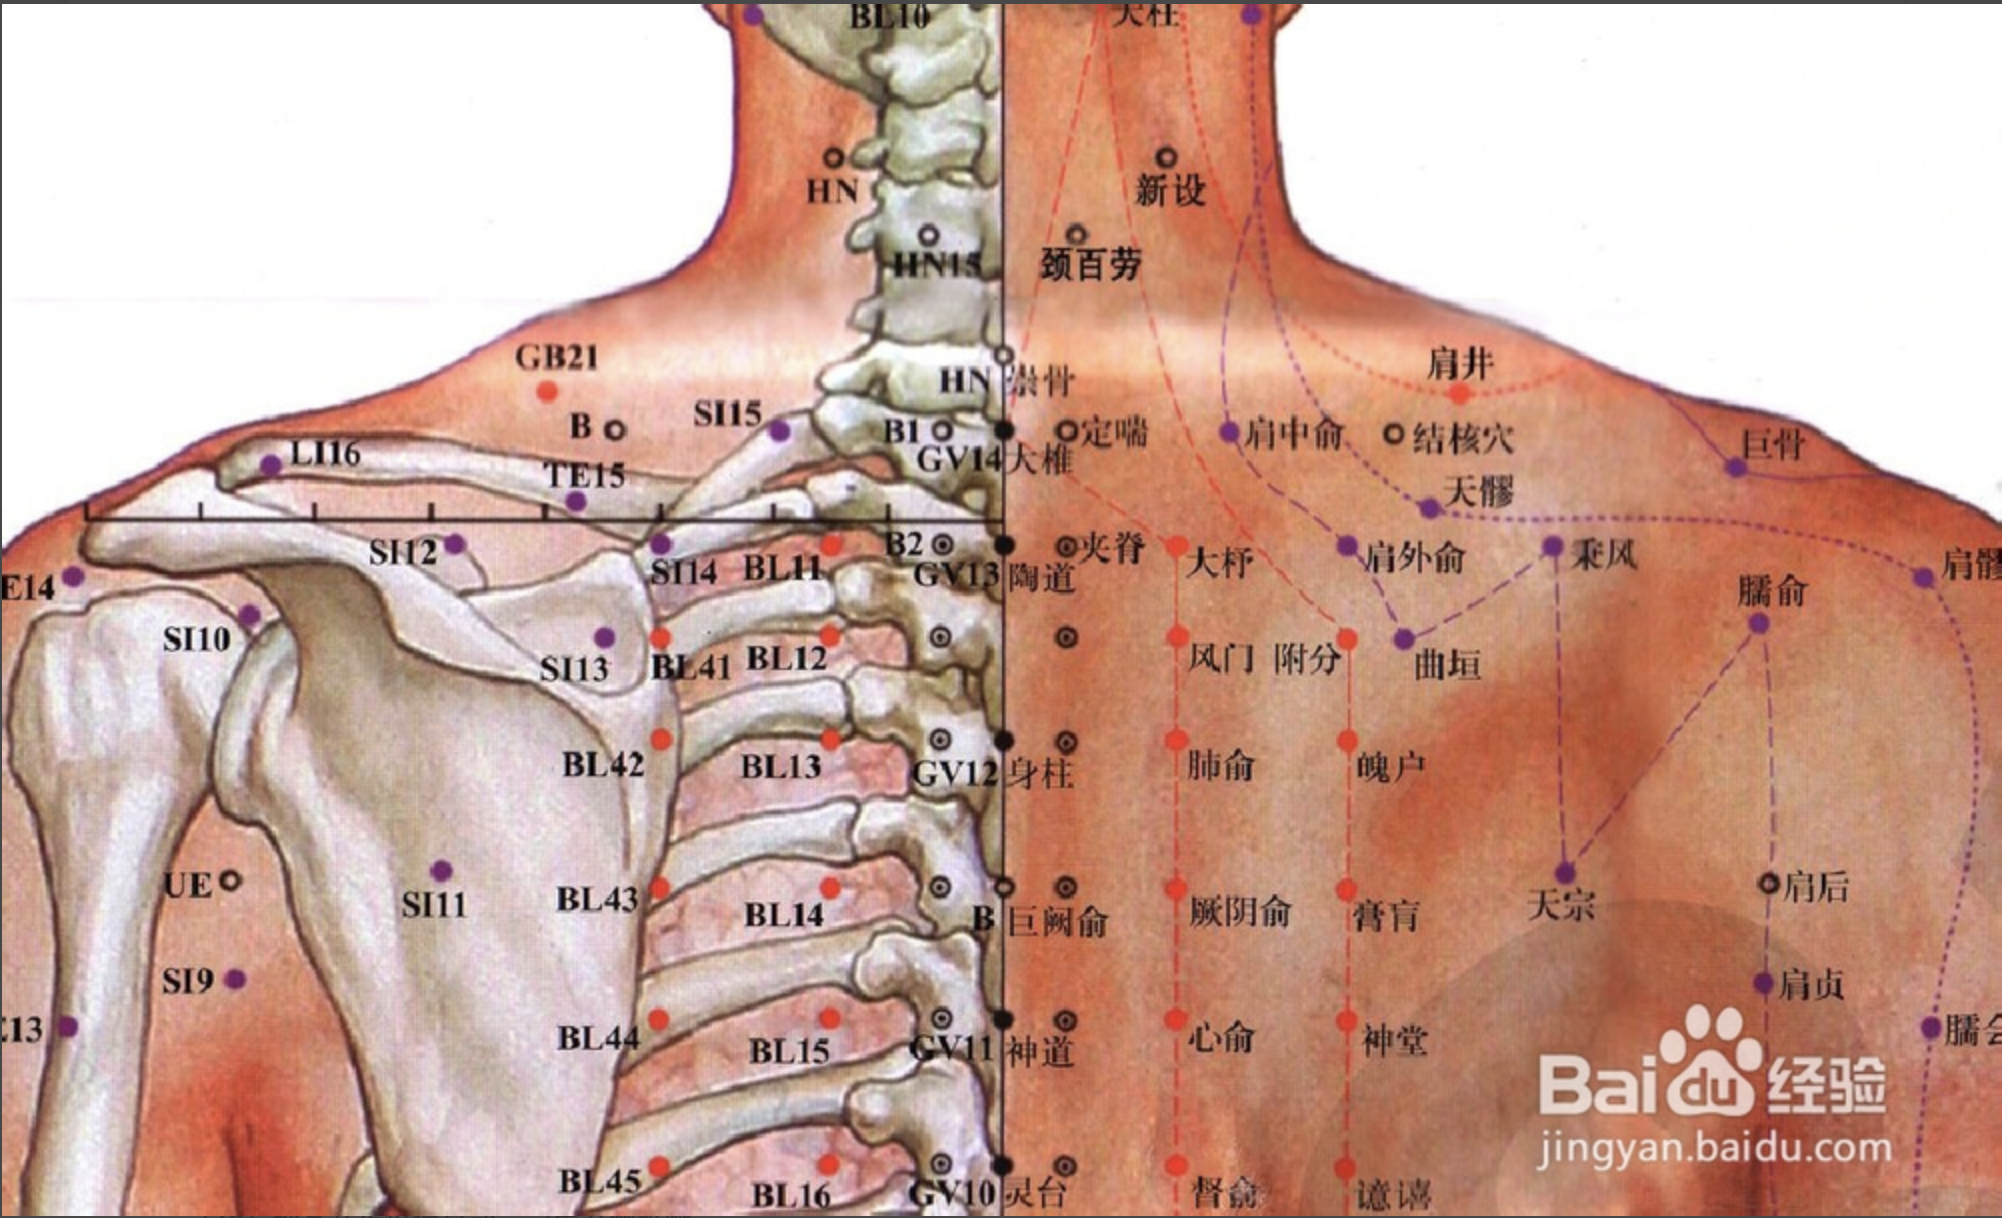

【(七)足太阳膀胱经(图 10-25-1)】

1、时辰 申时 15 ~ 17

2、歌诀 足太阳经六十七,精明目内红肉藏,攒竹眉冲与曲差,五处上寸半承光,通天络却玉枕昂,天柱后际大筋外,大杼(zhù)背部第二行,风门肺俞厥阴四,心俞督俞膈俞强,肝胆脾胃俱挨次。三焦肾气海大肠,关元小肠到膀胱,中膂(lǚ)白环仔细量,自从大杼至白环,各各节外寸半长,上髎次髎中复下,一空二空腰髁当,会阳阴尾骨外取,附分侠脊第三行,魄户膏肓与神堂。噫嘻膈关魂门九,阳纲意舍仍胃仓。肓门志室胞肓续,二十椎下秩边场,承扶臀横纹中央,殷门浮郗到委阳,委中合阳承筋是,承山飞扬踝附阳。昆仑仆参连申脉,金门京骨束骨忙,通谷至阴小指旁。

3、经脉循行 起于目内眦,上额交会于于巅顶(百会)。

巅顶部支脉:从头顶到颞(niè)颥(rú)部。

巅顶部直行的脉:从头顶入里联络于脑,回出分开下行项后,沿肩胛部内侧,夹脊柱,到达腰部,从脊旁肌肉进入体腔联络肾脏,属于膀胱。

腰部支脉:向下通过臀部,进入腘(guó)窝内。

后项部支脉:通过肩胛骨内缘直下,经过臀部下行,沿大腿后外侧与腰部下来的支脉会和于腘窝中。从此向下,出于外踝后,第五趾骨粗隆,至小指外侧端(至阴),与足少阴经相接。

4、主要病候 小便不通,遗尿,癫狂,疟疾,目痛,见风流泪,鼻塞多涕,鼻衄,头痛,项、背、臀部及下肢循行部位痛麻等。

3、主治概要 主治头、项、目、背、腰、下肢部病证及神志病,背部第一侧线的背俞穴及第二侧线相平的腧穴,主治与其相关的脏腑病证和有关的组织器官病证。

风门

【定位】 在背部,当第 2 胸椎棘(jí)突下,旁开 1.5 寸。

【主治】 伤风,咳嗽,发热头痛,项强,胸背痛。

【配伍】 配肺俞、大椎治咳嗽、气喘,配合谷治伤风咳嗽。

【刺灸法】 斜刺 0.5 ~ 0.8 寸。

【附注】 足太阳经与督脉交会穴。

肺俞

【定位】 在背部,当第 3 胸椎棘突下,旁开 1.5 寸。

【主治】 咳嗽,气喘,吐血,骨蒸,潮热,盗汗,鼻塞。

【配伍】 配风门治咳嗽喘,配合谷、迎香治鼻疾。

【刺灸法】 斜刺 0.5 ~ 0.8 寸。

【附注】 肺的背俞穴。

心俞

【定位】 在背部,当第 5 胸椎棘突下,旁开 1.5 寸。

【主治】 心痛,惊悸,咳嗽,吐血,失眠,健忘,盗汗,梦遗,癫痫。

【配伍】 配巨阙、内关治心痛,惊悸,配内关、神门治失眠、健忘。

【刺灸法】 斜刺 0.5 ~ 0.8 寸。

【附注】 心的背俞穴。

膈俞

【定位】 在背部,当第 7 胸椎棘突下,旁开 1.5 寸。

【主治】 呕吐,呃逆,气喘,咳嗽,吐血,潮热,盗汗。

【配伍】 配内关、足三里治呕吐、呃逆,配足三里、血海、膏肓治贫血。

【刺灸法】 斜刺 0.5 ~ 0.8 寸。

【附注】 (1)八会穴之一,血会膈俞。(2)参考资料:据报道,用人工放血造成家兔的贫血状态(红细胞在 4 × 10 ** 12 / L以下,血红蛋白在 65 g/L以下),针刺“膈俞”“膏肓”,结果与对照组相比,提前纠正了贫血状态,迅速恢复正常。

肝俞

【定位】 在背部,当第 9 胸椎棘突下,旁开 1.5 寸。

【主治】 黄疸,胁痛,吐血,目赤,目眩,雀目,癫狂痫,脊背痛。

【配伍】 配支沟、阳陵泉治胁痛,配太冲治目眩。

【刺灸法】 斜刺 0.5 ~ 0.8 寸。

【附注】 肝的背俞穴。

胆俞

【定位】 在背部,当第 10 胸椎棘突下,旁开 1.5 寸。

【主治】 黄疸,口苦,胁痛,肺痨,潮热。

【配伍】 配阳陵泉、太冲治胆道疾病。

【刺灸法】 斜刺 0.5 ~ 0.8 寸。

【附注】 胆的背俞穴。

脾俞

【定位】 在背部,当第 11 胸椎棘突下,旁开 1.5 寸。

【主治】 腹胀,黄疸,呕吐,泄泻,痢疾,便血,水肿,背痛。

【配伍】 配足三里治腹胀、便秘。

【刺灸法】 斜刺 0.5 ~ 0.8 寸。

【附注】 脾的背俞穴。

胃俞

【定位】 在背部,当第 12 胸椎棘突下,旁开 1.5 寸。

【主治】 胸胁痛,胃脘痛,呕吐,腹胀,肠鸣。

【配伍】 配中脘、梁丘治胃痛。

【刺灸法】 斜刺 0.5 ~ 0。8 寸。

【附注】 胃的背俞穴。

大椎

【定位】 在后正中线上,第 7 颈椎棘突下凹陷中(图 10-31-2)。

【主治】 热病,疟疾,咳嗽,喘逆,骨蒸潮热,项强,肩背痛,腰脊强,角弓反张,小儿惊风,癫狂痫证,五劳虚损,七伤乏力,中暑,霍乱,呕吐,黄疸,风疹。

【配伍】 配肺俞治虚损、盗汗、劳热,配间使、乳根治脾虚发疟,配四花穴治百日咳(双膈俞、双胆俞),配曲池预防流脑,配合谷治白细胞减少,配足三里、命门提高机体免疫力,配大椎、定喘、孔最治哮喘,配曲池、合谷泻热,配腰奇、间使治癫痫。

【刺灸法】 斜刺 0.5 ~ 1 寸;可灸。

哑门

【定位】 在项部,当后发际正中直上 0.5 寸,第 1 颈椎下。

【主治】 舌缓不语,音哑,头重,颈项强急,脊强反折,中风尸厥,癫狂,痫证,癔病,衄血,重舌,呕吐。

【配伍】 泻哑门、听会、外关(或中渚)、丘墟治高热或疟疾所致耳聋,配人中、廉泉治舌强不语、暴喑、咽喉炎,配百会、人中、丰隆、后溪治癫狂、癫痫。配风池、风府治中风失语、不省人事;配劳宫、三阴交、涌泉等九穴为回阳九针可以开窍醒神治昏厥,配脑户、百会、风池、太溪、昆仑、肾俞治大脑发育不全,针哑门、肾俞、太溪治疗贫血。

风门

【定位】 在背部,当第 2 胸椎棘(jí)突下,旁开 1.5 寸。

【主治】 伤风,咳嗽,发热头痛,项强,胸背痛。

【配伍】 配肺俞、大椎治咳嗽、气喘,配合谷治伤风咳嗽。

【刺灸法】 斜刺 0.5 ~ 0.8 寸。

肺俞

【定位】 在背部,当第 3 胸椎棘突下,旁开 1.5 寸。

【主治】 咳嗽,气喘,吐血,骨蒸,潮热,盗汗,鼻塞。

【配伍】 配风门治咳嗽喘,配合谷、迎香治鼻疾。

【刺灸法】 斜刺 0.5 ~ 0.8 寸。

【附注】 肺的背俞穴。

心俞

【定位】 在背部,当第 5 胸椎棘突下,旁开 1.5 寸。

【主治】 心痛,惊悸,咳嗽,吐血,失眠,健忘,盗汗,梦遗,癫痫。

【配伍】 配巨阙、内关治心痛,惊悸,配内关、神门治失眠、健忘。

【刺灸法】 斜刺 0.5 ~ 0.8 寸。

【附注】 心的背俞穴。

膈俞

【定位】 在背部,当第 7 胸椎棘突下,旁开 1.5 寸。

【主治】 呕吐,呃逆,气喘,咳嗽,吐血,潮热,盗汗。

【配伍】 配内关、足三里治呕吐、呃逆,配足三里、血海、膏肓治贫血。

【刺灸法】 斜刺 0.5 ~ 0.8 寸。

【附注】 (1)八会穴之一,血会膈俞。(2)参考资料:据报道,用人工放血造成家兔的贫血状态(红细胞在 4 × 10 ** 12 / L以下,血红蛋白在 65 g/L以下),针刺“膈俞”“膏肓”,结果与对照组相比,提前纠正了贫血状态,迅速恢复正常。

大椎

【定位】 在后正中线上,第 7 颈椎棘突下凹陷中(图 10-31-2)。

【主治】 热病,疟疾,咳嗽,喘逆,骨蒸潮热,项强,肩背痛,腰脊强,角弓反张,小儿惊风,癫狂痫证,五劳虚损,七伤乏力,中暑,霍乱,呕吐,黄疸,风疹。

【配伍】 配肺俞治虚损、盗汗、劳热,配间使、乳根治脾虚发疟,配四花穴治百日咳(双膈俞、双胆俞),配曲池预防流脑,配合谷治白细胞减少,配足三里、命门提高机体免疫力,配大椎、定喘、孔最治哮喘,配曲池、合谷泻热,配腰奇、间使治癫痫。

【刺灸法】 斜刺 0.5 ~ 1 寸;可灸。